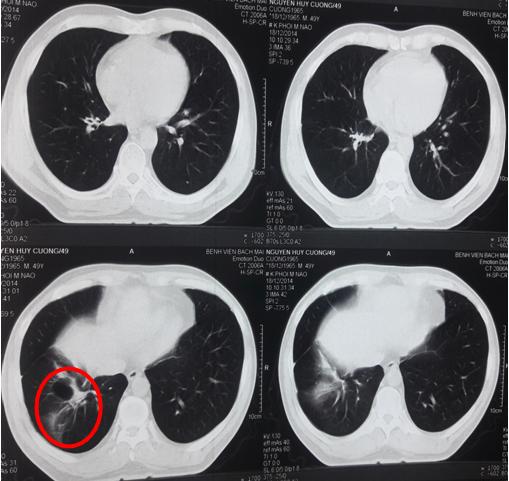

-       Chụp cắt lớp vi tính lồng ngực: U thùy dưới phổi phải kích thước 6 x 7cm, các nốt mờ rải rác 2 phổi.

Hình 1: Hình ảnh chụp cắt lớp vi tính lồng ngực trước điều trị (Vòng tròn đỏ: u thùy dưới phổi phải, kích thước 7 x 6cm, vòng tròn vàng: nốt vệ tinh phổi phải, vòng tròn xanh: nhân di căn phổi trái).